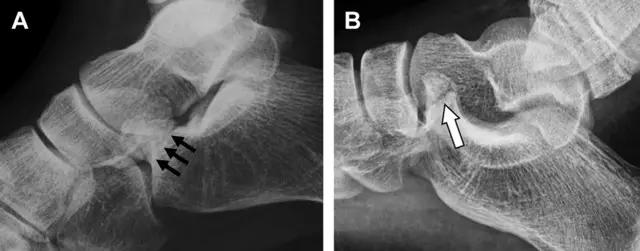

21趾短伸肌跟骨撕脱性骨折

另一种重要的跟骨撕脱性骨折,于足内翻时发生在趾短伸肌的起点处。观察来自跟骨背外侧的、不同大小的骨折块,前后位 X 片最适合不过了(图 7)。

图 7 溜冰受伤的患者,趾短伸肌跟骨撕脱性骨折。正位片示 2 个骨折块(箭头)来源于跟骨前外侧、趾短伸肌的起点处。踝关节外侧远端是否存在软组织水肿是一个重点观察点